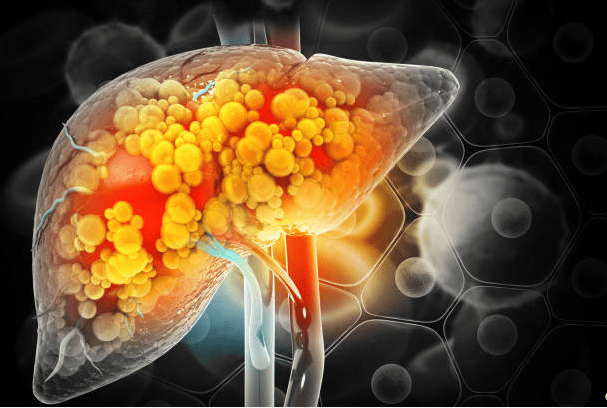

La depuració hepàtica és una forma controlada d’ajudar a l’organisme a què elimini toxines, la seva funció és accelerar la neteja hepàtica que es produeix al fetge de forma natural perquè el cos tingui el millor nivell d’eficiència, sobretot si per la nostra forma de vida acumulen un excés de toxines, o tenim els nostres òrgans inflamats i necessiten un suport per funcionar correctament.

El funcionament del fetge

Per si no n’hi hagués prou, el fetge té a veure amb més de cinc-centes funcions vitals en el nostre cos. Les més importants són: la producció biliar, la regulació del metabolisme dels lípids, produeix proteïnes a la sang i regula els aminoàcids, transforma el sucre en glucogen (fonamental pel rendiment esportiu), sintetitza el colesterol, emmagatzema el ferro, combat els bacteris que circulen per la nostra sang, regula la temuda coagulació sanguínia, i, en definitiva, depura el nostre cos, eliminant substàncies perilloses com ho són l’alcohol o les substàncies tòxiques del medicament. Mireu la importància d’aquest òrgan vital que emmagatzema el 13% de la nostra sang.